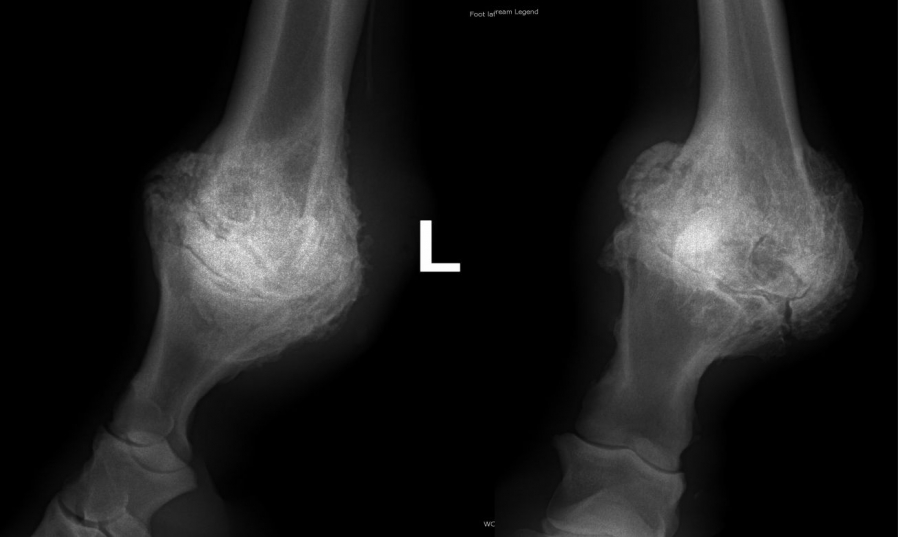

Ankylóza spěnkovýho kloubu

rentgenologické vyšetření

Těžká artróza ve spěnkovém kloubu